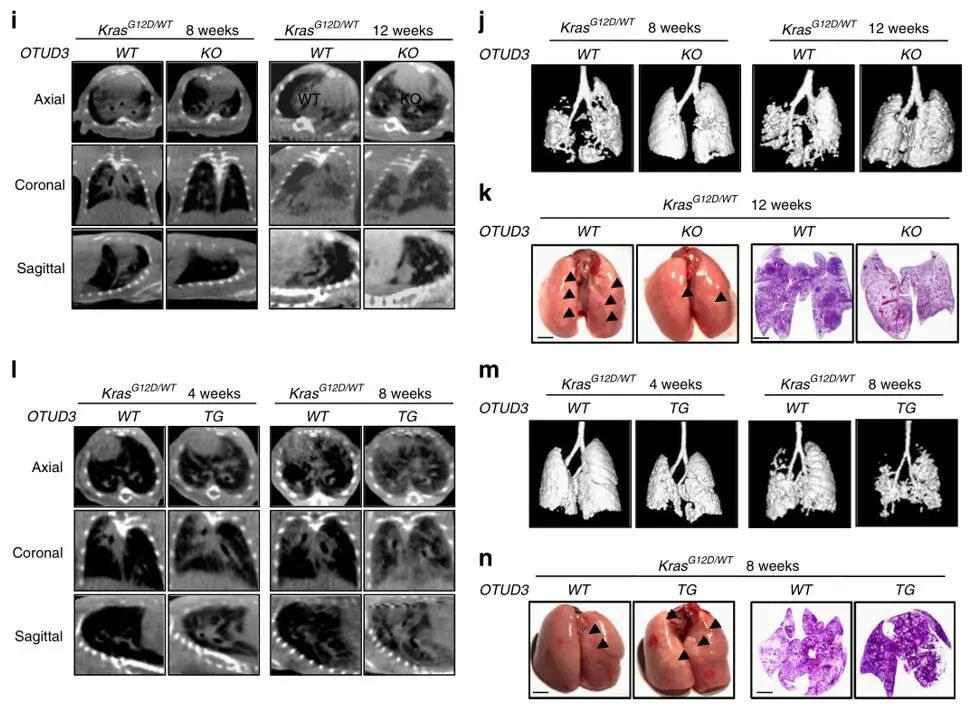

接着,为了揭示OTUD3在KrasG12D驱动的肺癌形成中的作用,作者构建了KrasLSL-G12D/WT/OTUD3 WT和KrasLSL-G12D/WT/OTUD3 KO小鼠。向KrasLSL-G12D/WT/OTUD3 WT和KrasLSL-G12D/WT/OTUD3 KO小鼠体内注射了表达Cre重组酶(AAV-Cre-GFP)的腺相关病毒,以诱导KrasG12D蛋白的表达。随后,作者对AAV-Cre诱导后12周的小鼠进行了分析,发现OTUD3基因的缺失导致生存期显著延长,与KrasG12D/WT/OTUD3 WT小鼠相比,KrasG12D/WT/OTUD3 KO小鼠肺部可检测到的结节更少、肿瘤负荷和肿瘤面积显著减少、肿瘤分级也较低。重要的是,KrasG12D/WT/OTUD3 KO小鼠的肿瘤切片表现出细胞增殖减少、血管生成萎缩和细胞凋亡信号积累。为了进一步确认OTUD3在肺癌中的致癌作用,作者将过表达OTUD3蛋白的OTUD3转基因(OTUD3 TG)小鼠与KrasLSL-G12D/WT/OTUD3 WT小鼠杂交,得到了KrasLSL-G12D/WT/OTUD3 TG小鼠。后续分析显示,KrasG12D/WT/OTUD3 TG小鼠肺部的可检测结节更多、肿瘤面积更大、肿瘤级别更高,且其总体生存率比携带正常OTUD3表达水平肿瘤的小鼠更差。此外,KrasG12D/WT/OTUD3 TG小鼠肿瘤组织中细胞增殖更快、血管生成更强、细胞凋亡率更低。以上得出结论:OTUD3在不同类型肿瘤中发挥独特作用,尤其值得注意的是,OTUD3在肺癌中并非充当肿瘤抑制因子,而是作为肿瘤促进因子发挥作用。

图2. OTUD3在肺癌中具有肿瘤促进作用